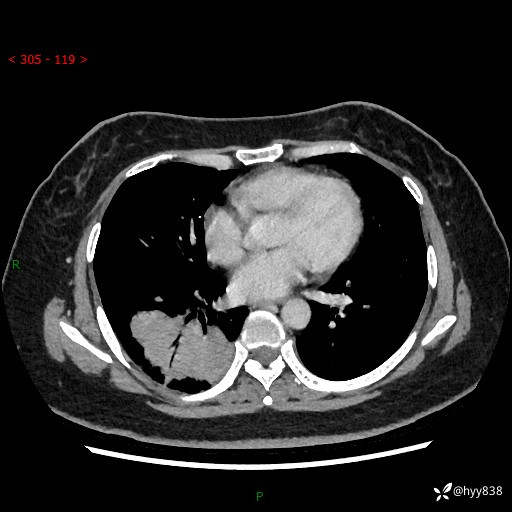

增强动脉期+静脉期